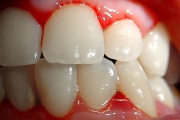

Krooniline gingiviit

Äge krooniline gingiviit

igemete veritsus kroonilise gingiviidiga patsiendil

Gingiviit ehk igemepõletik